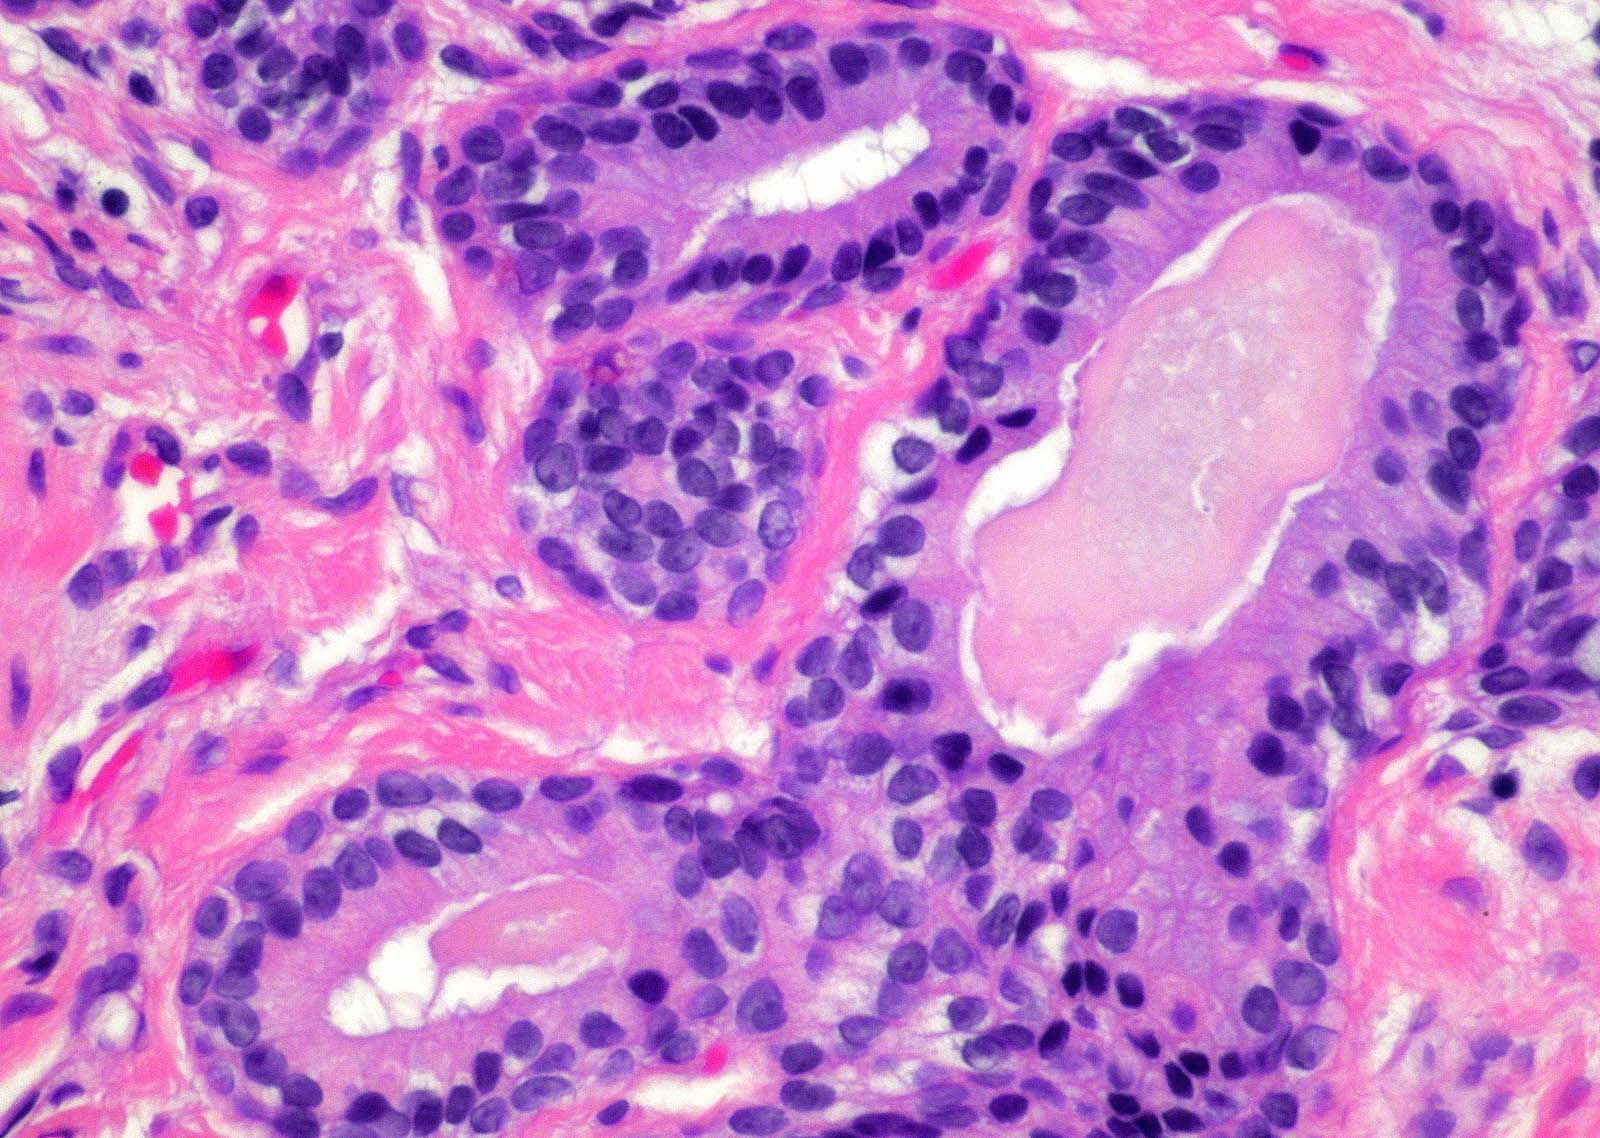

- Fibroepithelial urethral polyp (Am J Surg Pathol 2005;29:460):

- Pattern 1: most common pattern includes the following features

- Broad cloverleaf-like and club-like projections covered by normal urothelium and composed of dense fibrovascular stroma with florid cytitis cystica et glandularis (most common morphologic variant)

- Back to back glands present in the stalk

- Anastomosing nests of benign urothelial cells resembling inverted papilloma

- Dilated cysts with intracystic papillary contents

Microscopic (histologic) images

Contributed by Y. Albert Yeh, M.D., Ph.D.

Fibroepithelial polyp